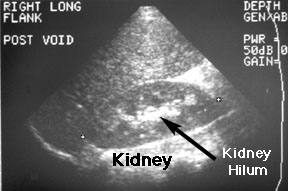

I am a first time mom in edmonton and my doctor asked me if i have a preference where i go to get my ultrasounds done. Where can i find free online ultrasound courses? Don't know where to go? Jump to navigation jump to search. Ultrasounds, also called sonograms, are used for diagnostic purposes and are a noninvasive method for your doctor to visualize your internal structures and organs. We are here for you. Here at the free pregnancy clinic, we provide limited obstetrical ultrasounds done by trained medical should this be the case, we will immediately advise you where to go for further care. Most often, this is found in the same general area as your network configuration screen.

I also drop color and doppler to get a pretty waveform if possible in each segment because i like to and i can, though most wouldn't consider it necessary in a normal. Where can i go to find a pregnancy center near me? How much an ultrasound costs you depends on where you get your ultrasound and your you can go to a planned parenthood near you, and they will have recources and advice to give you. I am a first time mom in edmonton and my doctor asked me if i have a preference where i go to get my ultrasounds done. To find out how pregnate your horse is, go to information in the reproduction tab, that is also where the information found by your ultrasound will appear. Other people think, that such records are needed to produce ultrasound. I was so nervous to get this ultrasound & now i don't really know how to feel at this point. An ultrasound — also called a sonogram — helps your doctor find out whether the fetus is developing normally. This article provides a beginners guide to ultrasound (pocus), including how ultrasound works and how ultrasound can be used in clinical practice. We are here for you. It may be dangerous and cause more problems under certain circumstances. An ultrasound/sonogram provides you with accurate information to date your pregnancy and to be sure it is not ectopic. A:it is common to read about the course on medical insurance processing while going through the article on where can i get an ultrasound in ocala.